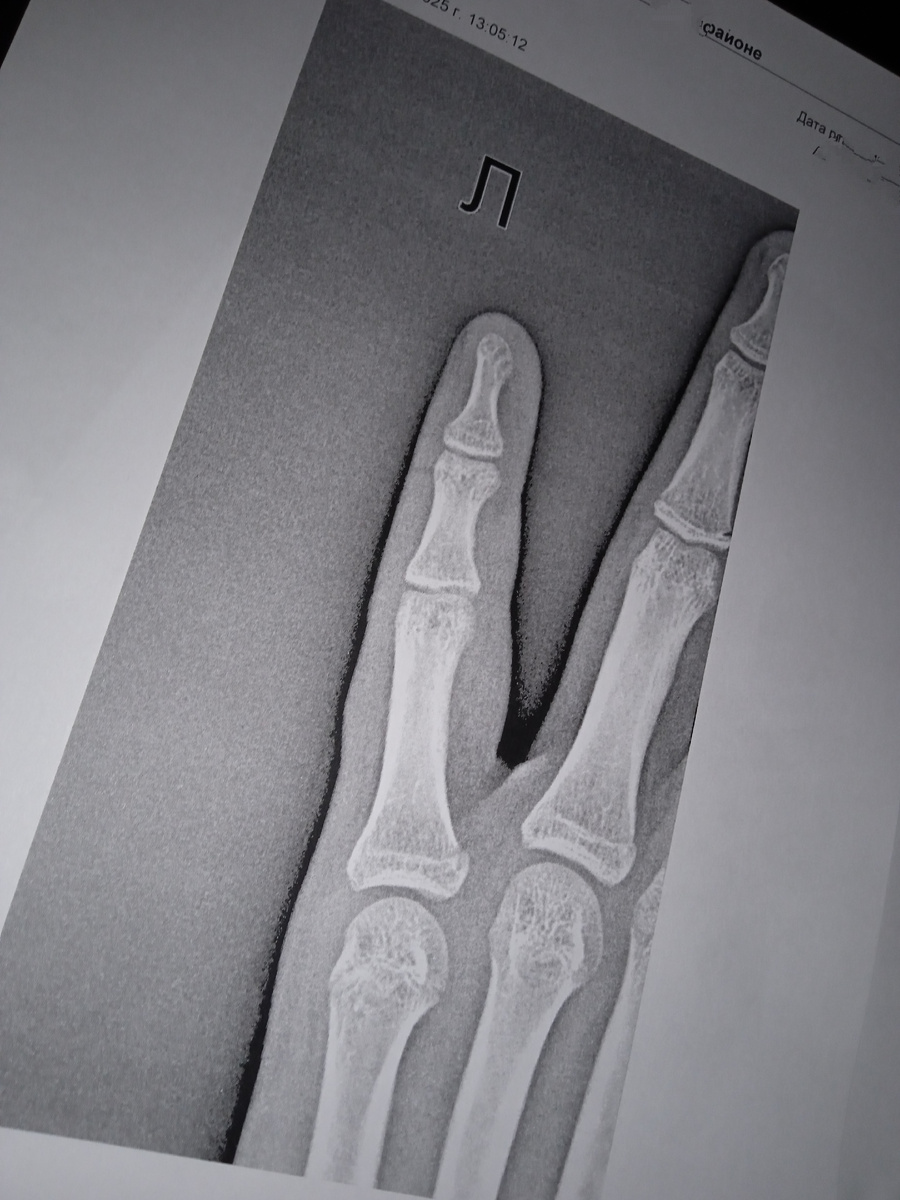

Здравствуйте. Вчера Вероника вернулась из школы с отёкшим и болезненным мизинцем. Она получила травму пальца на уроке физкультуры, когда в него попал мяч.

Почему я сначала пошла в лабораторию, а не к хирургу? Потому что хирург был в отпуске. Мне посоветовали ускорить процесс и обратиться в скорую помощь. Мы воспользовались этим советом и получили направление на рентген.

, сделали снимки, выдали описание и сами снимки сразу же.

Перелома нет, только ушиб.